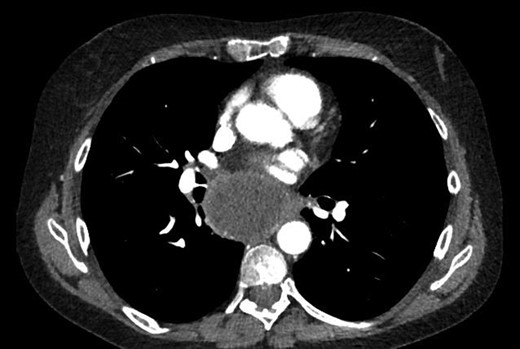

A 55-year-old Caucasian female presented with productive cough, dyspnea, chest pain and weight loss. The patient's medical history was significant for hypertension, hypercholesterolemia, dyslipidemia, chronic renal failure, gastroesophageal reflux disease and chronic anemia. She was a 30 pack-year smoker and her mother was diagnosed with lung cancer. Her physical examination was unremarkable. An initial chest X-ray showed a large subcarinal mass. On computed tomography (CT), a 6.2 × 5 cm tumor was detected in the subcarinal area (Figs 1 and 2). A bronchoscopy with transbronchial biopsy was performed, and the resulting pathological analysis was suspicious for malignant cells; however, no specific tumor type was identified. A positron emission tomography scan showed a large hypermetabolic subcarinal lesion with a standard uptake value of 14.3, consistent with malignancy. The differential diagnosis at the time included an infected bronchogenic cyst, esophageal duplication cyst or a malignant subcarinal lymph node. Thoracoscopic surgical resection was planned for diagnostic and therapeutic purposes.

Subcarinal tumor on preoperative CT of the chest, coronal cuts.